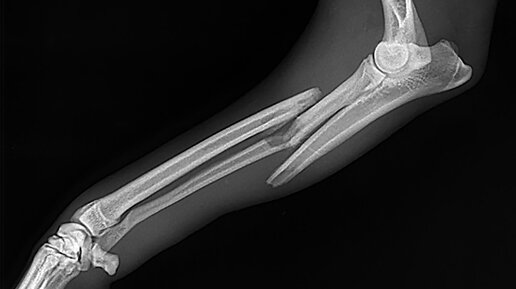

Жуткая история произошла с одним ребенком в Америке.   Мальчика доставили в больницу с острыми болями в животе, мышечной слабостью и сломанной рукой. Казалось бы, ничего необычного, но врачи не сразу оценили всю серьезность ситуации, и мальчик был направлен в обычное отделение. Пока он дожидался приема, он стал терять сознание и через некоторое время впал в кому. С мальчиком случилось что-то серьезное, неужели всему виной обычный перелом? Тут то и начинается наше небольшое расследование. Джейми (как мы его назовем для удобства) совсем недавно переехал с матерью в Америку...